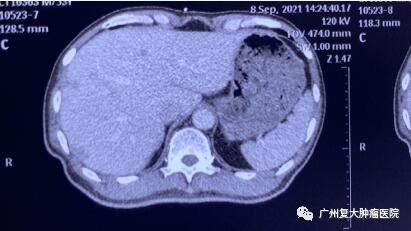

影像圖片顯示

圖1

為求進(jìn)一步診療,2020年11月,患者來(lái)廣州復(fù)大腫瘤醫(yī)院就診。入院完善相關(guān)檢查發(fā)現(xiàn):CA-199指標(biāo)高達(dá)2289u/ml(CA-199屬胃腸道腫瘤相關(guān)抗原,是一種腫瘤標(biāo)志物,正常值≤37u/ml);肝實(shí)質(zhì)內(nèi)有多個(gè)結(jié)節(jié)狀,較大者約4.3×3.8cm。胰腺體、尾部均有腫塊,并鄰近腸管、脾靜脈局部粘連不清,大小約4.3x3.3cm。